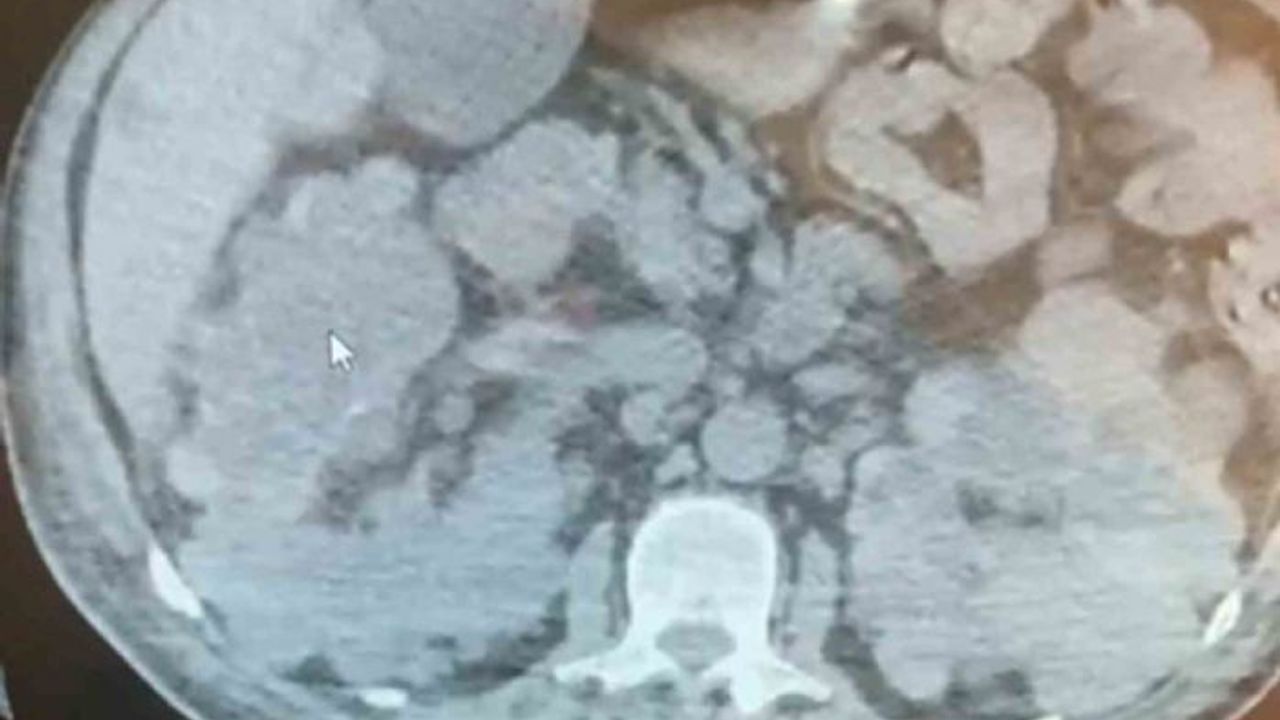

Yaklaşık 1 yıldır diyalize giren ve son 2 aydır ise sağ yan ağrısı, idrarda kanama, ara ara olan ateş şikayetleri ile Siirt Eğitim ve Araştırma Hastanesine başvuran 66 yaşındaki N.Y. adlı hasta, tedavi altına alındı.

Yapılan incelemelerden sonra ameliyata alınan hastaya 2 saatin sonunda polikistik böbrekte nefrektomi işlemi uygulandı. Başarıyla gerçekleştirilen ameliyatın ardından hasta 6 gün sonra komplikasyon olmadan taburcu edildi.